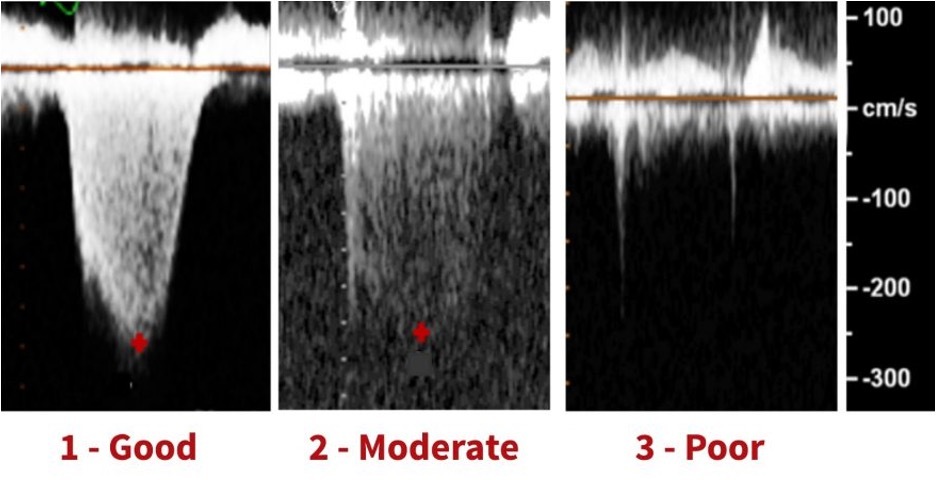

2. Gains adjustment

( to dark = lost in for and too bright = estimimation)